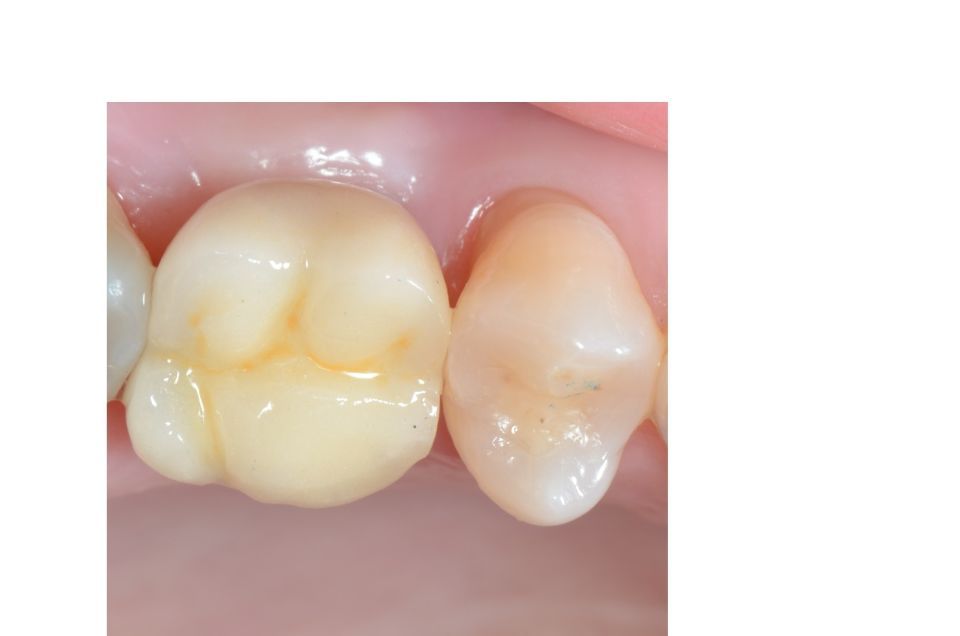

Prosthetic rehabilitation

Oral rehabilitation is the part of dentistry that is concerned with restoring oral aesthetics and harmony through dental prostheses, always looking for a correct occlusion and function. It integrally combines the areas of fixed prosthesis, removable prosthesis, operative, occlusion and dental implant.

When carrying out the treatment plan, appropriate to the patient, an attempt will be made to recover their oral health through the most modern rehabilitation techniques; establishing a close relationship with the other disciplines of dentistry, such as periodontics, endodontics and orthodontics. To achieve the best result.

By means of current dental techniques, it is possible to carry out these restorations by means of fixed prostheses on teeth or dental implants in more than 95% of patients, thus avoiding the use of removable prostheses that are always uncomfortable and in many cases impossible to bear.

One of the techniques most used today thanks to technological advances, is digital oral rehabilitation or digital flow.